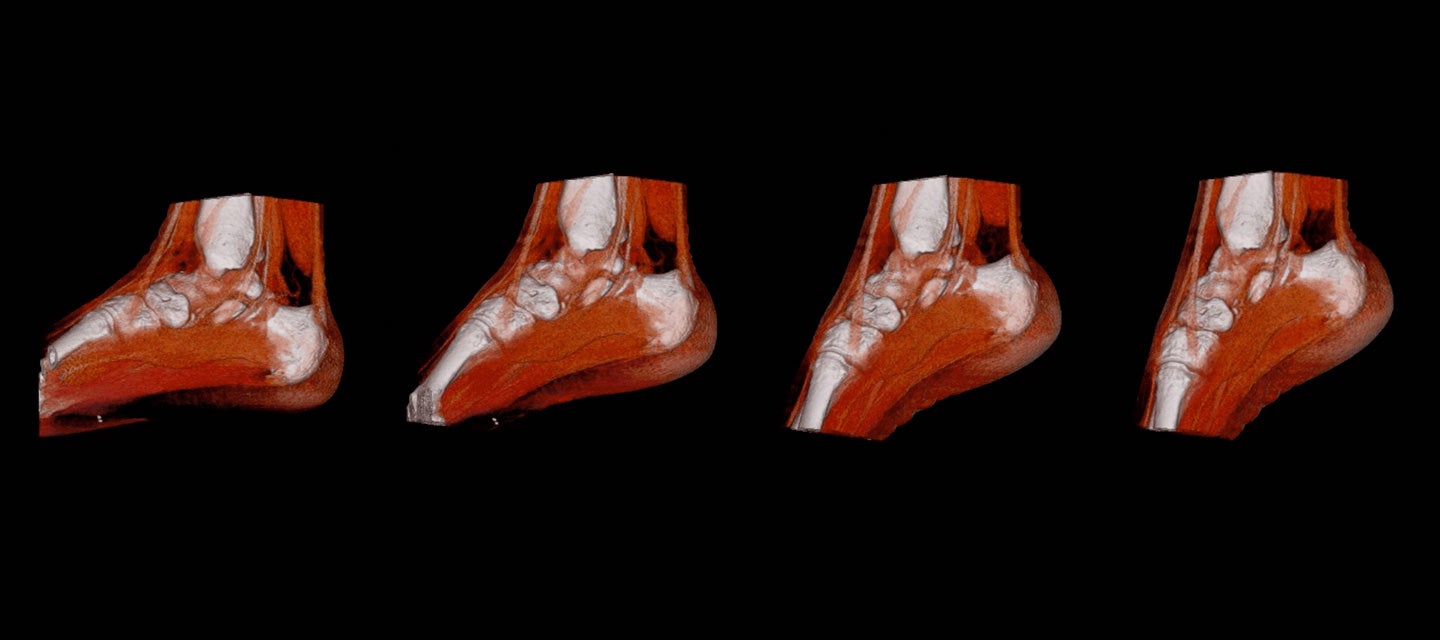

Podiatry

With a wide number of injuries and conditions to treat, our referring podiatrists depend on I-MED Radiology’s range of diagnostic imaging capabilities, in particular ultrasound and x-ray. With imaging and reports available online at I-MED Online, we can help you to quickly confirm a diagnosis and ensure the most effective management for your patients.

Dynamic 4D CT